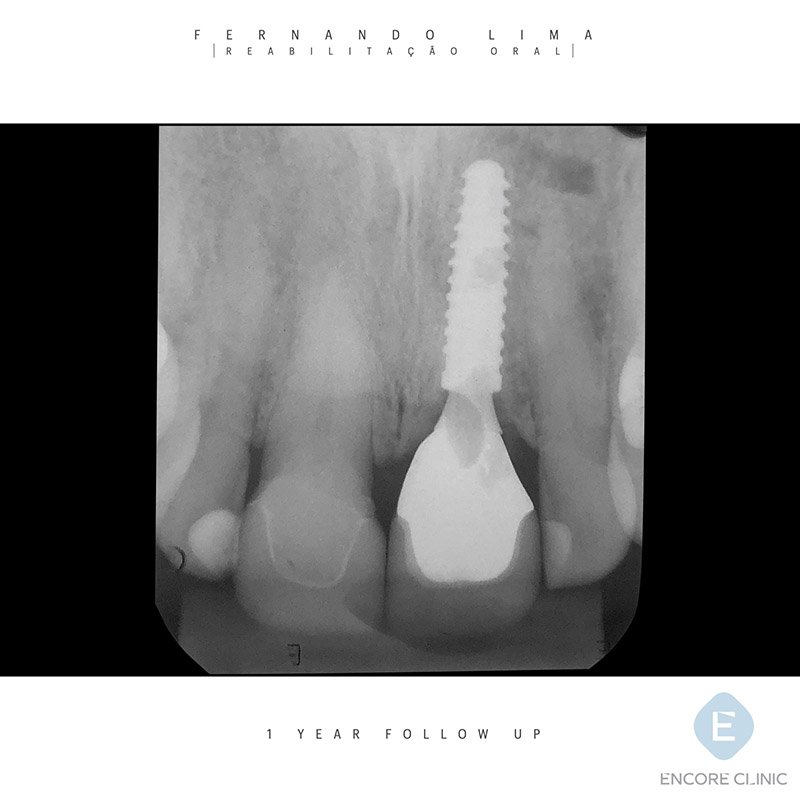

Nesse caso, optamos em utilizar o implante Due Cone 3.5×13 com pilar provisório CM 4.0×2.5 mm.

A reabilitação final foi conduzida com infraestrutura de zircônia sobre Pilar Base T 3.5×2.5 mm e confecção de duas coroas em dissilicato de lítio nos elementos 11 e 21.

Após um ano de acompanhamento, podemos observar a estabilidade dimensional das margens gengivais, ausência de inflamação e preservação das cristas ósseas interproximais.